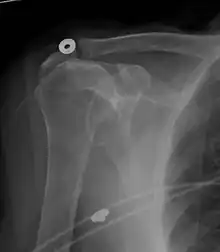

A complete tear of the supraspinatus resulting in a shift upwards of the head of the humerus

Diagnosis is based upon physical assessment and history, including description of previous activities and acute or chronic symptoms. A systematic physical examination of the shoulder comprises inspection, palpation, range of motion, provocative tests to reproduce the symptoms, neurological examination, and strength testing.[31] The shoulder should also be examined for tenderness and deformity. Since pain arising from the neck is frequently 'referred' to the shoulder, the examination should include an assessment of the cervical spine looking for evidence suggestive of a pinched nerve, osteoarthritis, or rheumatoid arthritis.